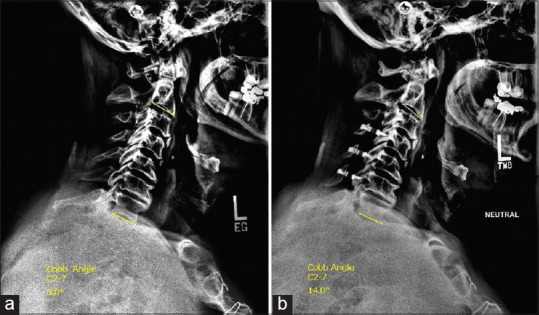

Materials and methods: A retrospective review was conducted on cervical myelopathy patients treated with laminoplasty between January 2019 and January 2022 at a tertiary care center. Inclusion criteria included pre- and 1-year postoperative X-rays and magnetic resonance imaging within 6 months presurgery. PKD was defined as loss of cervical lordosis greater than -10° based on the C2-7 Cobb angle. Fatty infiltration was evaluated using Goutallier classification and voxel quantification.

Results: Among 44 patients, 4 developed PKD. Qualitatively, 32 patients were classified as Goutallier 0-1.5, 6 were Goutallier 1.5-2.5, and 6 Goutallier 2.5-4. There is a significant association between the Goutallier grade and PKD occurrence after 1 year (P = 0.00085). Quantitatively, the average fatty infiltration percentage for the kyphotic patients was 23.3% ± 5.81% versus 13.8% ± 9.83% for nonkyphotic patients. A significant association was found between the percentage of fatty infiltration and the PKD after 1 year (P = 0.045). The optimal fat cutoff between kyphotic and nonkyphotic patients was 23% (P = 0.056).